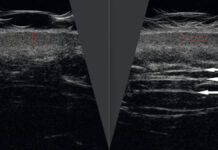

Ocena kliniczna wpływu iniekcji nieusieciowanego kwasu hialuronowego na parametry skóry z oznakami starzenia. Studium...

STRESZCZENIEJedną z najpopularniejszych metod niwelowania oznak starzenia skóry twarzy są zabiegi iniekcyjne z zastosowaniem nieusieciowanego kwasu hialuronowego.Celem badania była ocena skuteczności terapii z wykorzystaniem...